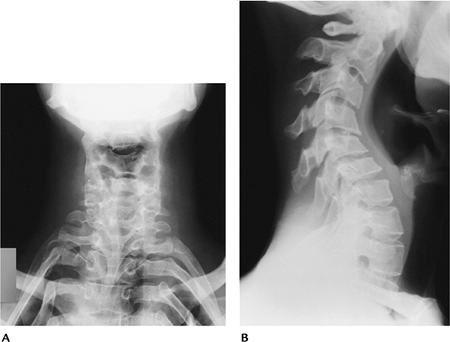

Radiographic features:

Subcutaneous calcifications resembling phleboliths on the extensor surfaces of the forearms and legs

Joint effusions, hemarthrosis, and subluxations

Spinal deformity and scoliosis result from ligament laxity

Posterior vertebral scalloping secondary to dural ectasia

FIGURE 15-24 Ehlers-Danlos syndrome. AP (A) and lateral (B) radiographs of the cervical spine showing exaggeration of the cervical curves.